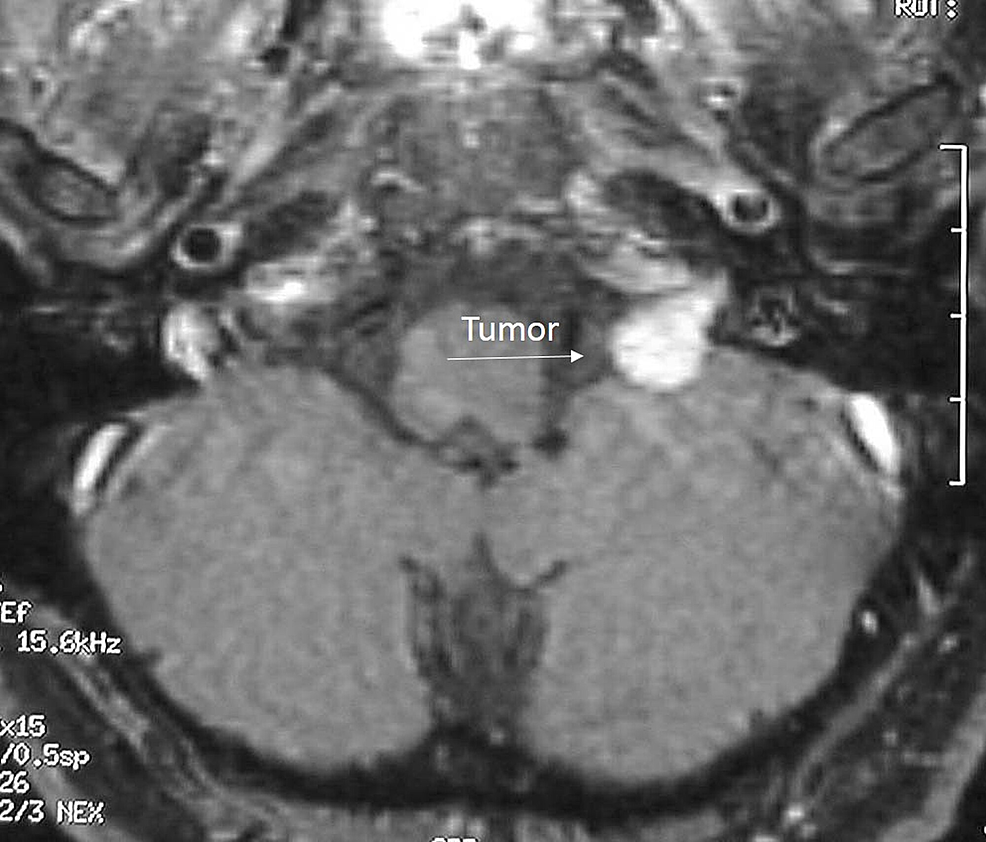

Case study 42 intracranial neoplasm image This picture illustrates case study 42 intracranial neoplasm.

Intracranial tumors picture This image shows Intracranial tumors.

Case study 42 intracranial neoplasm fiction and non-fiction creative composition prompts will aid writers expand their imagination. It should beryllium kept in brain that an related to intracranial lipoma tail also exist, if the patient has symp. Acoustic neuroma is the most common benign tumor atomic number 85 cerebellopontine angle. Objective to assess the jeopardy of meningioma related to with use of high dose cyproterone acetate, a progestin indicated for medical institution hyperandrogenism. Participants 253 777 girls and women aged 7-70 days living in France who started cyproterone acetate between 2007. Background myopericytomas are benignant soft tissue tumors which are seldom found as intracranial masses.